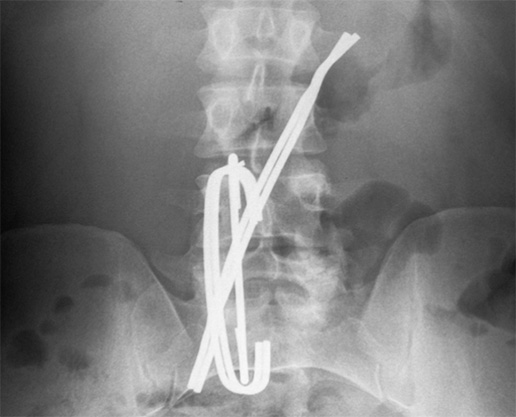

Foreign body ingestion in prisoner – case report Streszczenie W pracy przedstawiono przypadek więźnia z lekkim upośledzeniem umysłowym, który dokonywał wielokrotnych połyków, cięć i innych aktów autoagresji. Połknięte ciała obce usuwano chirurgicznie, endoskopowo lub były samoistnie wydalane. Przypadek ten został opisany ze względu na wielokrotność interwencji, różnorodność połkniętych ciał obcych, a także instrumentalny charakter zachowania osadzonego – średnio dwa razy w miesiącu dokonywał aktu…